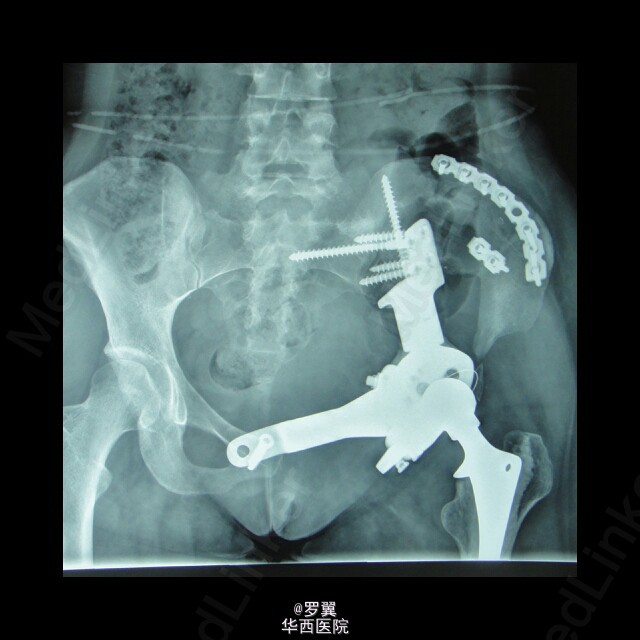

骨盆恶性肿瘤半骨盆假体置换术后髂骨断裂

患者23岁女性,骨盆恶性肿瘤半骨盆假体置换术后,进行髂骨保留并予钢板螺钉内固定,术后2年残留髂骨疲劳断裂。。